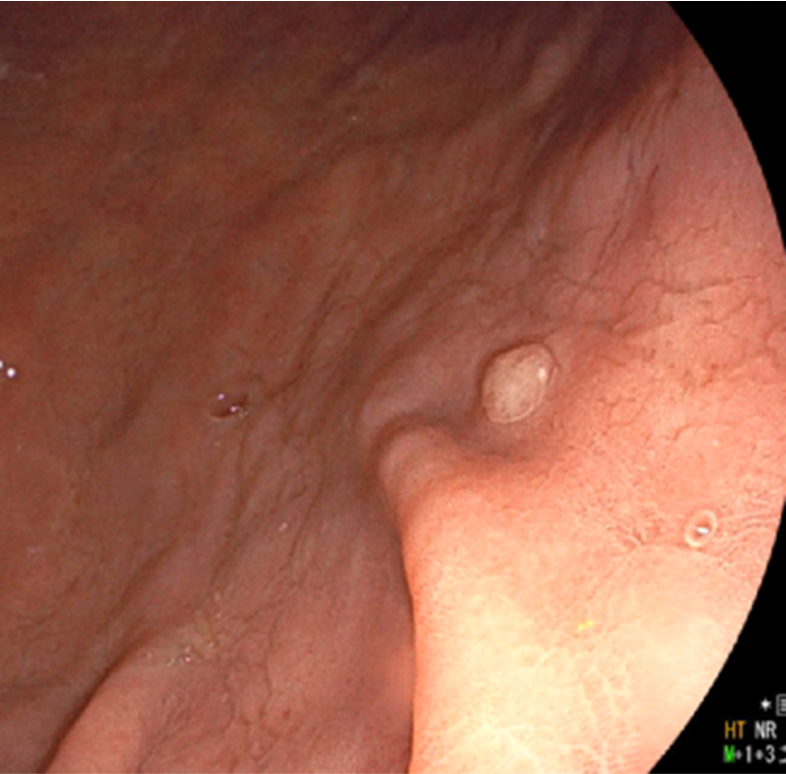

胃底腺ポリープ